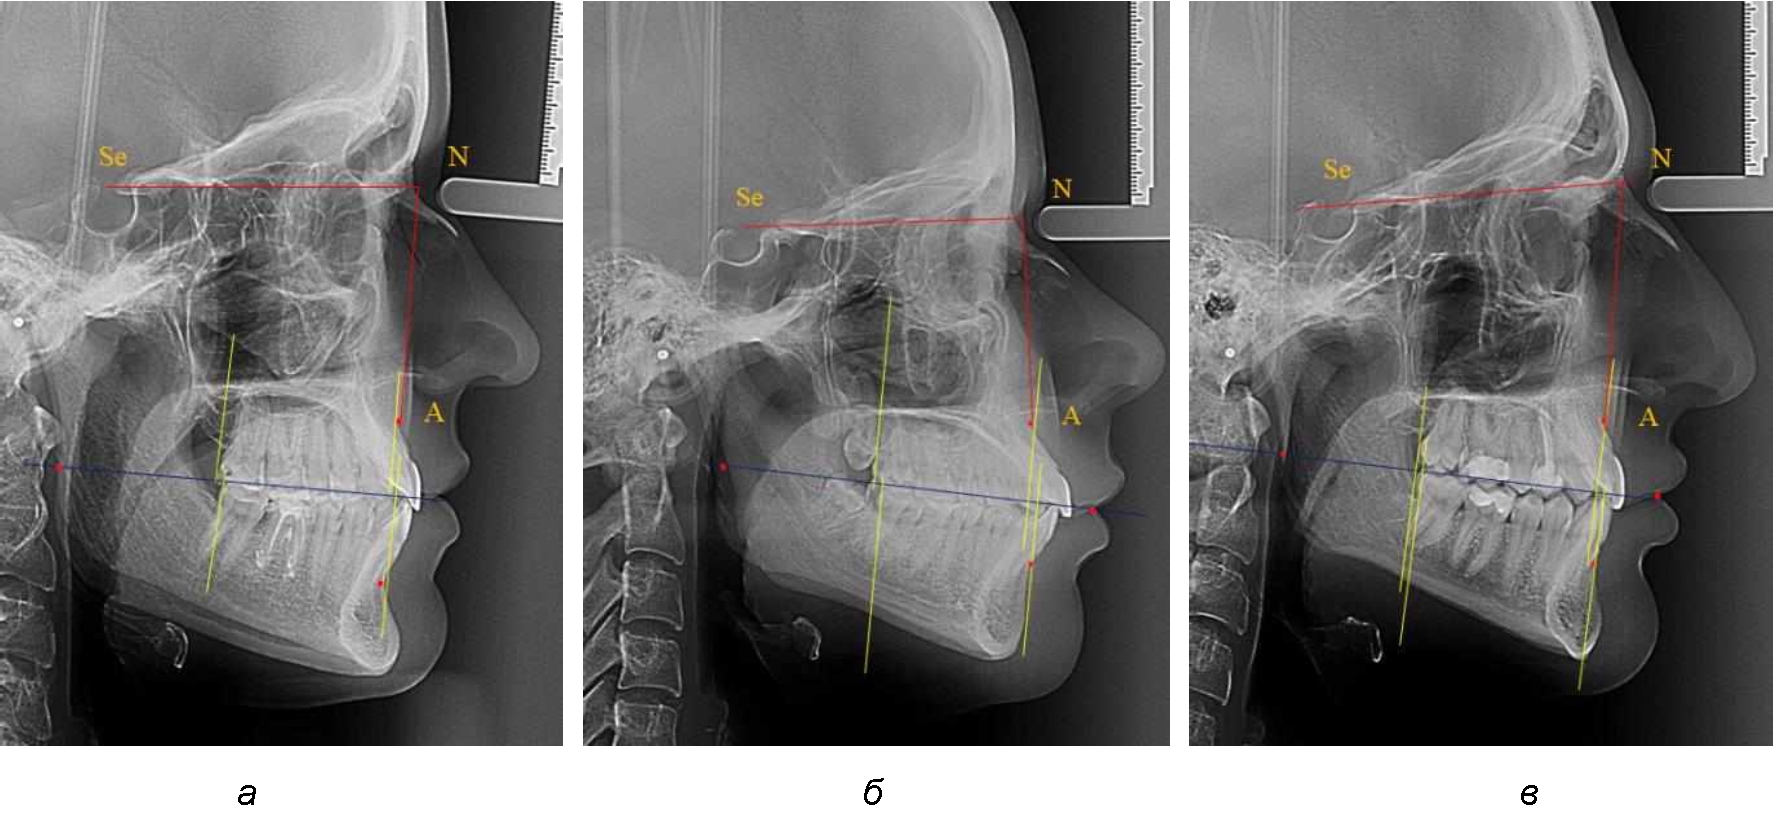

На рентгенограммах устанавливали точки Downs. На верхней челюсти субспинальная точка A(SS) располагалась в наиболее вогнутой точке альвеолярного отростка по переднему его краю. На нижней челюсти супраментальная точка B(SM) соответствовала месту наибольшей вогнутости переднего края альвеолярной части. Окклюзионную линию проводили через контактную точку резцов (vРOcP) и дистальную точку окклюзии второго нижнего моляра (hРOcP). Место пересечения окклюзионной линии с дистальным краем ветви нижней челюсти (ramus mandibule) обозначали как «rmРOcP». Перпендикулярно к окклюзионной плоскости проводили линии из точек «А(SS)» и «В(SМ)», что определяло их проекцию на окклюзионную линию. Аналогично отмечали положения дистальных окклюзионных точек верхней и нижней челюсти (рис. 1).

Рис. 1. Положение основных точек (а) и линейных ориентиров (б) для анализа положения и размеров челюстей

Альвеолярно-дентальный размер верхней челюсти и нижней челюсти оценивали по окклюзионной линии между вертикалями, ограничивающими исследуемые челюсти. Положение верхней челюсти оценивали по величине размера «rmOcP-А», а нижней челюсти по расстоянию «rmOcP-В». Линия смыкания губ обозначалась как точка «sto», вблизи которой проходила окклюзионная линия. Данный ориентир позволял провести окклюзионную плоскость при аномалиях положения резцов в вертикальном направлении, когда была сложность определения резцовой окклюзионной точки (vРOcP).

При анализе рентгенограмм, было отмечено, что на 26 снимках из 58 [(44,83 ± 6,53) %] отмечалась нормопозиция верхней челюсти. При этом средняя величина лицевого угла (ANSe) составила (85,04 ± 0,56)°, и пациенты были отнесены к 1-й группе 1-й подгруппе. Антепозиция верхней челюсти была отмечена на 20 те-лерентгенограммах [(34,483 ± 6,24) %], при этом величина лицевого угла составляла (89,12 ± 0,62)°. Ретропозиция была отмечена на 12 рентгенограммах [(20,69 ± 5,32) %], а средняя величина лицевого угла составляла (80,21 ± 0,48)°.

При всех вариантах положения верхней челюсти, было отмечено, что альвеолярно-денталь-ные размеры верхних зубо-челюстных дуг были близки по значению к аналогичным размерам нижней челюсти и разница в размерах не превышала 1,0–1,5 мм, а средняя величина различия показателей составляла (1,07 ± 0,54) мм.

Расстояние от конструируемой точки окклюзионной плоскости на ветви челюсти («rmРOcP») до апикальных точек Downs на обеих челюстях также коррелировало между собой, и средняя величина различия показателей составляла (1,23 ± 0,69) мм. Проекция нижней апикальной точки на окклюзионную линию, как правило, располагалась несколько кпереди проекции верхней апикальной точки, на величину около 1 мм, что соответствовало оптимальным данным Wits-анализа.

Аналогичное расстояние было отмечено и при расположении дистальных окклюзионных точек верхней и нижней челюсти (рис. 2).

Рис. 2. Положение апикальных точек и челюстей при нормопозиции (а), антепозиции (б) и ретропозиции (в) верхней челюсти